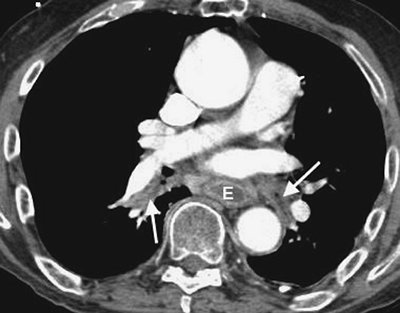

FIGURE 17-9. Mucous plugging. CTPA of a 75-year-old man with an esophageal stricture and gastroesophageal reflux shows a dilated esophagus (E) and low-attenuation material within the lower lobe segmental bronchi (arrows). The adjacent pulmonary vessels enhance normally.

FIGURE 17-10. Mucous plugging. A: CTPA shows low-attenuation material occluding the right lower lobe subsegmental bronchi (arrow). The adjacent pulmonary vessels enhance normally. B: Coronal CT shows the impacted right lower lobe bronchi (arrows) adjacent to normally enhancing pulmonary vessels.